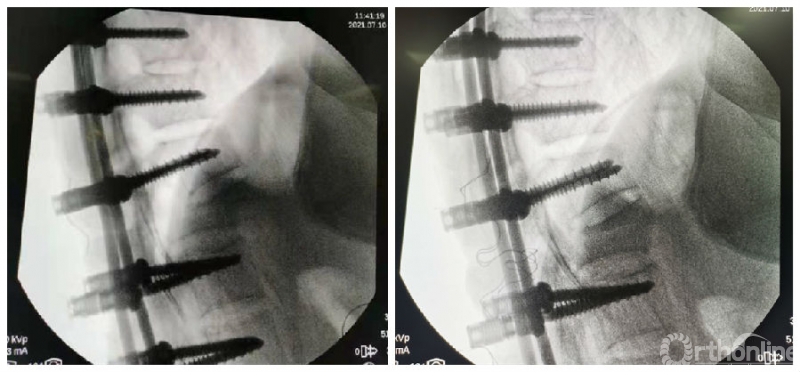

经椎弓根椎体楔形截骨术(pedicle subtraction osteotomy, PSO)作为相对安全有效的三柱截骨方式而被广泛应用于AS胸腰段后凸畸形的矫形治疗,通过胸腰段及腰段的单节段或双节段的PSO可使脊柱后凸畸形得到有效的矫正。该术式避免前柱的过度延长,降低了大血管损伤的并发症,截骨面积大,有利于实现坚固的骨性融合。

由于三柱截骨矫形术中脊柱处于极度不稳定状态,在截骨间隙闭合过程中部分患者出现矢状面移位(sagittal translation,ST),导致硬膜囊前方出现骨性台阶,理论上增加硬膜囊和神经根卡压的风险,造成灾难性的后果,影响手术的综合疗效。近年来ST受到越来越多的关注,多数以病例报道形式,现就其研究进展做一综述。

Chang最早报道矢状面移位,定义为截骨平面头侧椎体后下缘与尾侧椎体后上缘之间位移超过2mm[1]。成俊遥:<4mm的ST较难避免且通常无明显诱发因素,可视作截骨操作误差范围[2]。ST判定标准的不同导致其发生率的报道存在着较大的差异(1.6%-27%)。

ST的复位对于神经的减压更直接有效,并可以避免椎板和神经根切除减压过程中硬膜损伤风险。复位主要通过调整截骨平面上下椎体置钉深度以及调整矫形棒铰链点水平进行。

尽管在调整置钉深度过程中取下一侧矫形棒存在进一步加重矢状位脱位的风险,笔者认为已经发生的ST上下截骨面多数处于嵌插位置,暂时处于稳定状态,此时在保留对侧矫形棒固定的状态下,交替进行椎体置钉深度和矫形棒铰链点水平的调整是相对安全的。